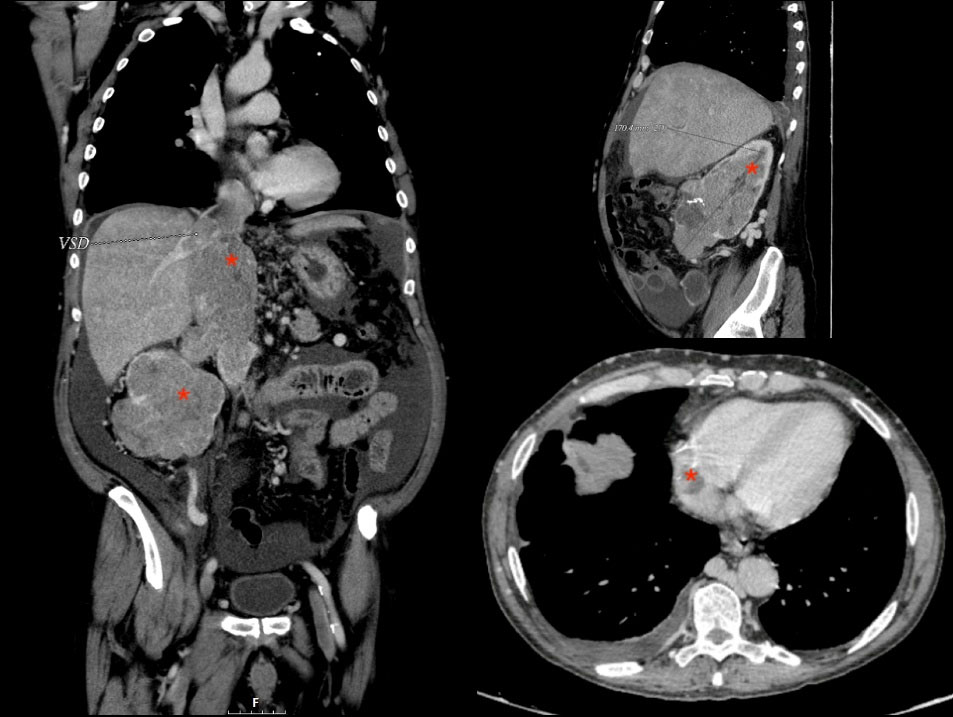

The postoperative period of the patients consisted of a short stay in the Intensive Care Unit and subsequent transfer to the ward where a control CT scan was performed prior to discharge. Figure 5 shows cuts of the postoperative CT of one of the patients, demonstrating the absence of thrombus.

Figure 5.

Images from the postoperative CT scan of one of the patients, demonstrating the absence of thrombus. The regressed regions are marked with an asterisk